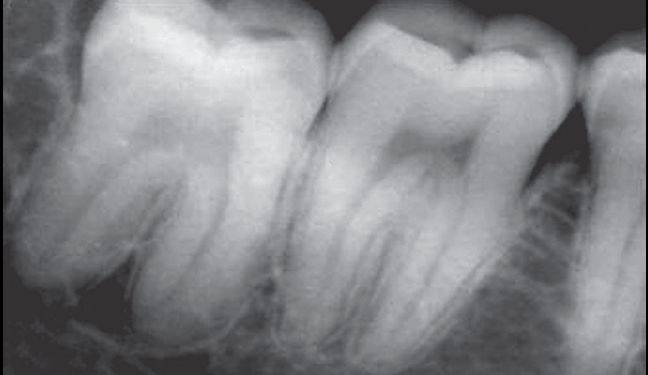

根部阻力亦可称根部骨阻力或牙根阻力。根部阻力主要根据X线片分析,阻力大小与牙位、牙根数目、牙根形态、根尖形态、根周骨组织情况有关。

牙根阻力以多根牙、根分歧过大、特长根、U形根、牙颈部倒凹大者阻力较大根尖区以近中弯曲、多向弯曲、根尖肥大者牙根阻力较大。

根部阻力较大者的智齿形态